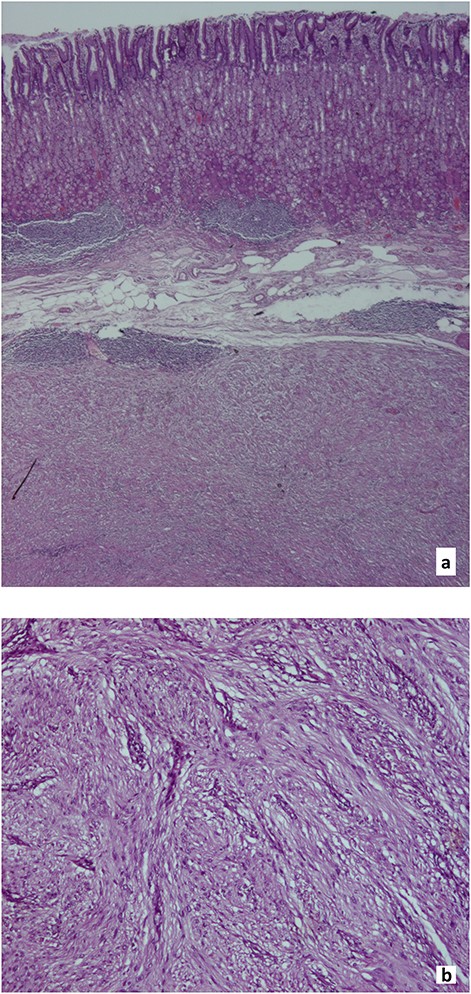

Histological findings, gastric schwannoma: a. Muscularis propria tumour, surrounded by peripheral lymphoid aggregates (Hematoxylin and eosin, x20). b. Spindle cells with palisading nuclei, arranged in a fascicular pattern with rare mitosis (1/30 high-power field) and no necrosis (Hematoxylin and eosin, x100).

Inspection of surgical specimen (Fig. 4) showed an intramural, nodular, solid mass measuring 85 × 60 × 60mm with unremarkable overlaying mucosa; a cut section revealed a yellowish homogeneous tumour. Histological examination (Fig. 5) revealed a well-delimited, but not capsulated mass, centred at muscularis propria, surrounded by peripheral lymphoid aggregates. Spindle cells with palisading nuclei, arranged in a fascicular pattern, slight pleomorphic, rare mitosis (1/30 high-power field) and no necrosis characterized this tumour. Resection margins were negative for tumour cells. Additionally, immunohistochemistry of tumour cells showed strongly positive nuclear staining for S-100 (Fig. 6) and SOX10, consistent with the diagnosis of benign schwannoma.